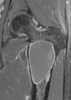

Simple unicameral bone cyst

A bone cyst or geode is a cyst that forms in bone. Types include: Unicameral bone cyst Aneurysmal bone cyst Traumatic bone cyst Diagnosis On CT scans, bone cysts that have a radiodensity of 20 Hounsfield units (HU) or less, and are osteolytic, tend to be aneurysmal bone cysts.In contrast, intraosseous lipomas have a lower radiodensity of -40 to -60 HU. Treatment and Prevention Simple (Unicameral) Bone Cyst Some unicameral bone cysts may spontaneously resolve without medical intervention. [Source: Wikipedia ]